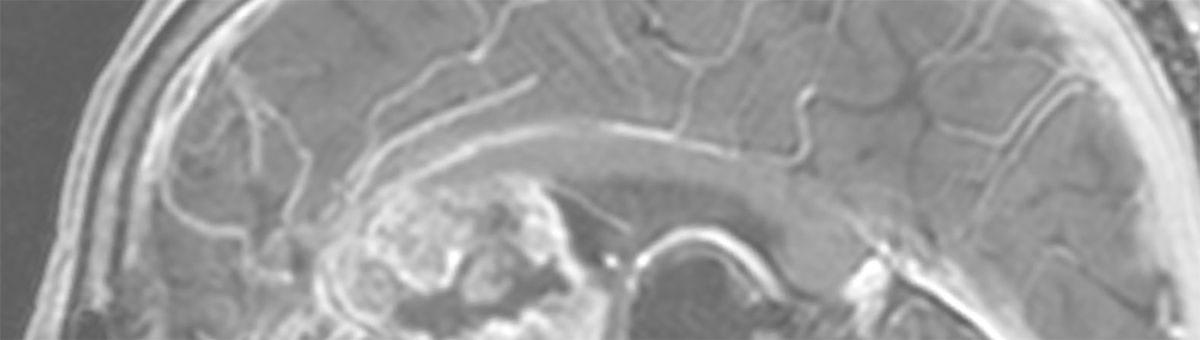

Kurativt syftande radioterapi ges i regel fem dagar i veckan under en period av fyra till åtta veckor i en process som kallas fraktionerad strålbehandling. Detta behandlingsmönster ökar effekten av terapin genom att förstärka skillnader i responsen för strålning mellan tumör och omkringliggande frisk vävnad. För att behandlingen skall bli framgångsrik måste tumören träffas av behandlingsfälten vid varje fraktion. Med hjälp av speciell fixeringsutrustning, laserlinjer, hudmarkeringar och avancerad bildtagning i behandlingsrummen kan patienten noggrant positioneras enligt planeringen vid varje behandlingstillfälle. Det är därför särskilt viktigt att undvika systematiska fel, det vill säga fel som introduceras i planeringsstadiet och sedan påverkar alla fraktioner på samma sätt. Ett sådant fel kan innebära att en del av tumören konsekvent hamnar utanför strålfältet, vilket drastiskt minskar chansen för bot. Modern strålbehandling av cancer planeras i dag i stor utsträckning på datortomografiska bilder (CT). Dessa utnyttjas dels för att identifiera tumörens position inför behandlingen, men också för att kunna utföra noggranna beräkningar av hur strålning absorberas i kroppen – sådana simuleringar, som också kallas dosplanering, är nödvändiga för att bestämma hur behandlingen skall ges för att åstadkomma bästa möjliga resultat. Vid en datortomografi mäts röntgenstrålningens absorption, eller attenuering, i kroppen, vilket är precis den information som behövs för att kunna göra en noggrann dosberäkning.